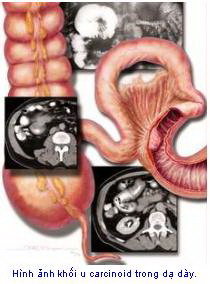

Các u carcinoid có nhiều điểm khác với các loại

ung thư thông thường. Nó phát triển rất chậm và ít khi có triệu chứng trừ khi ở

giai đoạn muộn. Ngay cả khi xem dưới kính hiển vi thì các u carcinoid vẫn có vẻ

như bình thường, thậm chí ở cả giai đoạn nó đã có di căn. U carcinoid có thể

sản xuất và phóng thích các hormon vào cơ thể và gây ra các triệu chứng bất

thường, ví dụ như tiêu chảy hay cơn nóng bừng mặt.